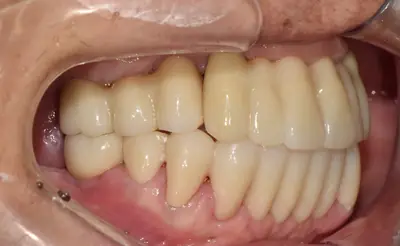

치과 치료를 두려워하는 분들을 위해, 진정요법을 활용한 사례를 소개합니다. 부산에 거주하던 60대 여성 환자가 치아가 많이 손상되어 임플란트와 브릿지 치료를 받았는데, 병원 트라우마와 공포로 어려움이 있었어요. 의식하 진정요법을 통해 깊은 낮잠 같은 상태에서 안전하게 치료를 받았고, 수술 과정도 성공적이었어요. 이 방법은 전신마취보다 안전하고, 환자도 큰 두려움 없이 치료를 마칠 수 있어요. 치과 공포증이 심한 분들도 전문가와 상담 후 진정요법을 고려해보시면 좋겠습니다.